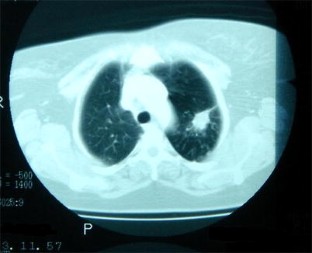

Abb. 1